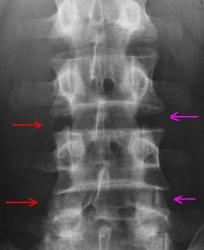

Молодой мужчина с болями в спине.

Предлагаю коллегам высказать свое мнение по представленным снимкам. Исследование выполнено в положении стоя, снимки размещены в высоком разрешении.

Уважаемые коллеги! Позволю себе начать. По представленным рентгенограммам, кроме spina bifida S1 позвонка, других патологических изменений не выявлено. Высота тел позвонков, межпозвонковых промежутков равномерная. Имеется слабо выраженный сколиоз поясничного отдела влево (вероятно, за счет болевого синдрома). Причин болей в спине масса!

Хорошо, я в целом разделяю мнение Др. Ермолаева, данных за дегенеративный спондилёз/дискоз не вижу (и не писал); в дополнение к дефекту левой задней дужки S1 позвонка, имеет место быть частичная люмбализация 1го крестцового позвонка (не уверен как правильно по русски, я написал: "partial S1 lumbalization (transitional vertebra)". Описание нормы я опускаю.

А меня напрягают дугоотросчатые сочленения в L4 - S1. Верхние края суст. пов-тей верхних суставных отростков (нижележащего п-ка) заходят за края нижних (суст. отростков вышележащего п-ка)

Буквально почти все мои находки уже опубликованы. Осталось полторы штуки. Деф. спондилоартроз сочленения (неоартроза) S1-2 справа – на стороне частичной люмбализации S1, а также левосторонний сколиоз Iст. с ротацией, вершина дуги на уровне L4-5 (возможно это антальгическая поза) . Ещё выбухание диска L2-3 и кпереди и кзади, но это может быть показалось. А спондилоартроз в L4-5-S1 не поддерживаю.

Пол и примерный возраст озвучены в оглавлении поста (Молодой мужчина с болями в спине.), конкретнее-возраст около 30 лет.

По поперечному отростку: естественно это артефакт, Nela уже объяснила (Кажется эта линия выходит за контур поперечного отростка, значит артефакт.)

По поводу дефекта дужки: как Вы смогли прочитать выше; я также написал именно дефект дужки, а не s.bifida, т.к. spiona bifida это нарушения сращения задней арки, и здесь данный термин неуместен.

По поводу остистых отростков: организм человека не механизм, и остистые отростки не обязательно должны быть в "одну линию", я расцениваю это как вариант анатомии и индивидуального строения (лицо человека, крылья носа, даже глаза бывают асимметричными, но это не является признаком наличия патологии.

rentgenb1 прав в отношении оценки люмбализации, я уже писал выше, что S1 transitional vertebra, т.е. переходной позвонок; т.к. нет исследования всего позвоночника.

Как видите, большинство мнений по основным находкам на данных рентгенограммах сошлись, именно на основании наличия объективных фактов, которые нельзя трактовать двояким образом. Я рад.

Пациенту выполнили МРТ, нашли кисту Тарлова, чем и объяснили боли. В межпозвонковых дисках патологии не обнаружили, все ядра без признаков дегидратации (значит говорить и дискозе нельзя), в позвонках-без патологии.